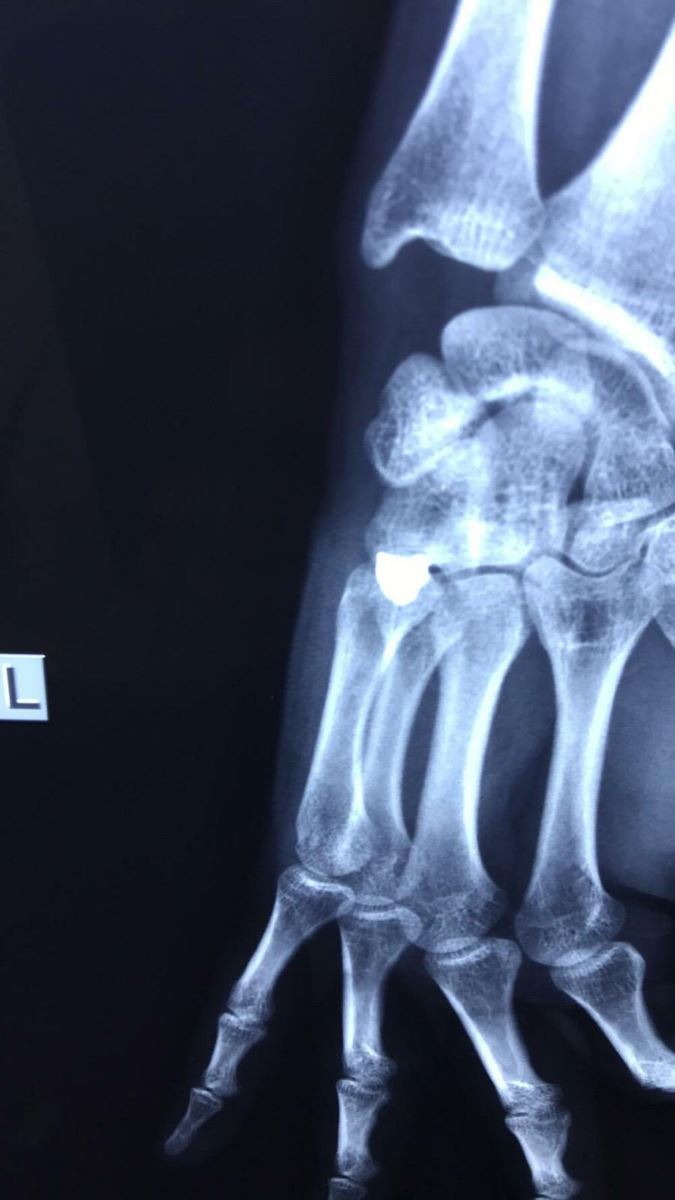

Pogledajte i fotografije rendgentskog snimka povređenog mladića i fotografiju metka kojim je ranjen Miloš:

Na jednoj fotografiji se vidi rentgenski snimak šake pre operacije sa sve metkom koji se nalazi unutar tela, a na drugoj metak koji je izvađen nakon operacije u KBC Gračanica.